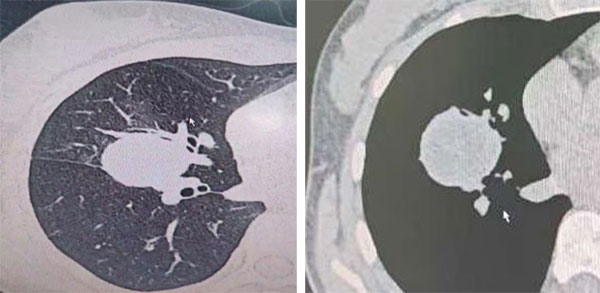

患者,17岁女性,居住在牧区。因体检发现右肺占位,到拉萨市人民医院就诊后收入院。在胸外科、麻醉科、呼吸内科、重症医学科等多学科MDT团队讨论和论证下,考虑肺包虫病,遂决定给患者实施单孔胸腔镜右肺中叶切除术,达到包虫的根治目的。在曹小庆的带领下,经过MDT的充分评估后制定出详细的手术方案,3小时后手术顺利完成,术中出血不多,目前患者已康复出院。

术前CT影像资料